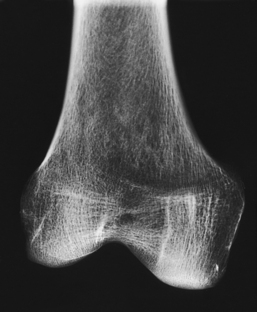

The general features of most bones are shown in Fig. 3-12. All bones are composed of a strong, dense outer layer called the compact bone and an inner portion of less dense spongy bone. The hard outer compact bone protects the bone and gives it strength for supporting the body. The softer spongy bone contains a spiculated network of interconnecting spaces called the trabeculae (Fig. 3-13). The trabeculae are filled with red and yellow marrow. Red marrow produces red and white blood cells, and yellow marrow stores adipose (fat) cells. Long bones have a central cavity called the medullary cavity, which contains trabeculae filled with yellow marrow. In long bones, the red marrow is concentrated at the ends of the bone and not in the medullary cavity.

A tough, fibrous connective tissue called the periosteum covers all bony surfaces except the articular surfaces, which are covered by the articular cartilage. The tissue lining the medullary cavity of bones is called the endosteum. Bones contain various knoblike projections called tubercles and tuberosities, which are covered by the periosteum. Muscles, tendons, and ligaments attach to the periosteum at these projections. Blood vessels and nerves enter and exit the bone through the periosteum.